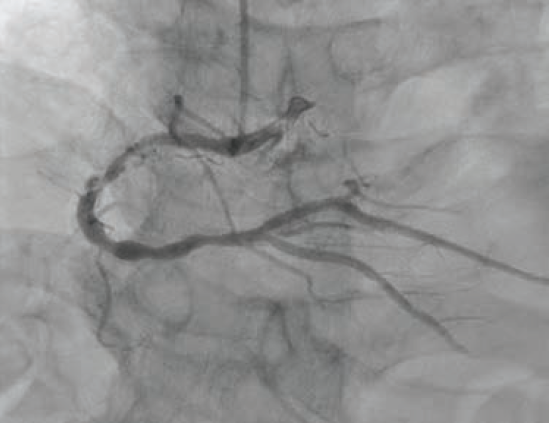

An 80-year-old male with hypertension, dyslipidemia, type 2 diabetes mellitus, chronic kidney disease stage IIIa, and known coronary artery disease (CAD) with recent PCI to the left anterior descending (LAD) artery presented to our emergency department (ED) with recurrent unstable angina. Ten days prior, he underwent coronary angiography for unstable angina and was found to have a 90% mid-LAD lesion that was stented with a 2.5 mm x 28 mm Synergy™ drug-eluting stent (DES) (Boston Scientific). Also present was severe calcific disease of the proximal and mid right coronary artery (RCA) (Figure 1); the plan was for staged PCI of the RCA in 4 weeks. However, prior to the planned procedure and due to recurrent unstable angina, the patient was sent back to the hospital by his primary care physician. On arrival, his electrocardiogram showed no ischemic changes, and serial high-sensitivity troponins were minimally elevated and flat.

A 6 French AL 0.75 guide catheter was used to engage the ostium of the RCA. A Runthrough® NS Extra Floppy coronary guidewire was placed in the right posterolateral branch, while a Runthrough NS Izanai™ wire coronary guidewire was advanced to the right posterior descending artery (RPDA) as a buddy wire. Initial predilation was attempted with a 2.5 mm x 15 mm NC Euphora™ balloon (Medtronic), but this would not pass the lesion. A 6 French LiquID® guide catheter extension (Seigla Medical) was introduced for additional guide support. Despite this, the 2.5 mm NC Euphora™ was still unable to reach the area of interest without pushing out the guide. A 2.5 mm x 15 mm NC Takeru™ PTCA balloon dilation catheter was used instead, and was successfully brought to the diseased segment and inflated to high pressure. The rest of the proximal and mid vessel was also pre-dilated with the same balloon. We still could not bring the 6 French Opticross™ HD IVUS catheter (Boston Scientific) to the desired area due to the calcific nodule. Therefore, a 2.5 mm x 12 mm C2+ IVL balloon (Shockwave Medical) was used to deliver 70 total pulses to the mid RCA. This was followed by a 3.0 mm x 12 mm C2+ IVL balloon, with which 90 pulses were administered at 4-6 atmospheres (atm) each. Angiography showed reasonable luminal gain (Figure 2).